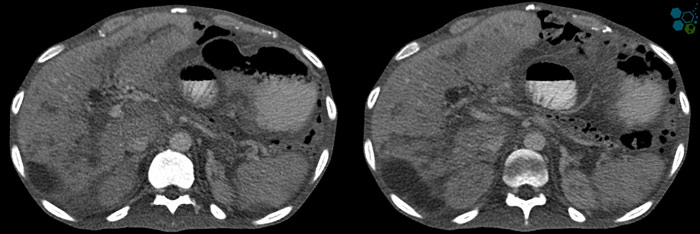

Each year, hundreds of thousands of people around the globe experience having some sort of pancreatitis. Pancreatitis is defined as the inflammation of the pancreas. Pancreatitis occurs when the enzymes trypsin become activated. If you suspect that you may have pancreatitis, it is very important that you consult with a Pancreatic specialist or Endocrinologist in your home country immediately. There are several reasons why we develop pancreatitis but the overwhelming cause for most pancreatitis is due to frequent alcohol intake and gallstones. Eating and drinking habits play the biggest role in those afflicted with this degenerative disease.

Acute vs Chronic Pancreatitis

Most clinical studies have proven that the leading causes of pancreatitis are attributed to alcohol and gallstones. For chronic pancreatitis, alcohol is the common etiology while acute pancreatitis is attributed to gallstones. Chances are if you like to drink a lot and you have a sedentary lifestyle, you are putting yourself at a huge risk of developing liver Cirrhosis, kidney disease, Erectile dysfunction , heart disease and/or chronic pancreatic disease.